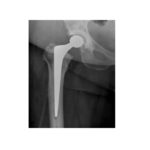

Shareable Image—-